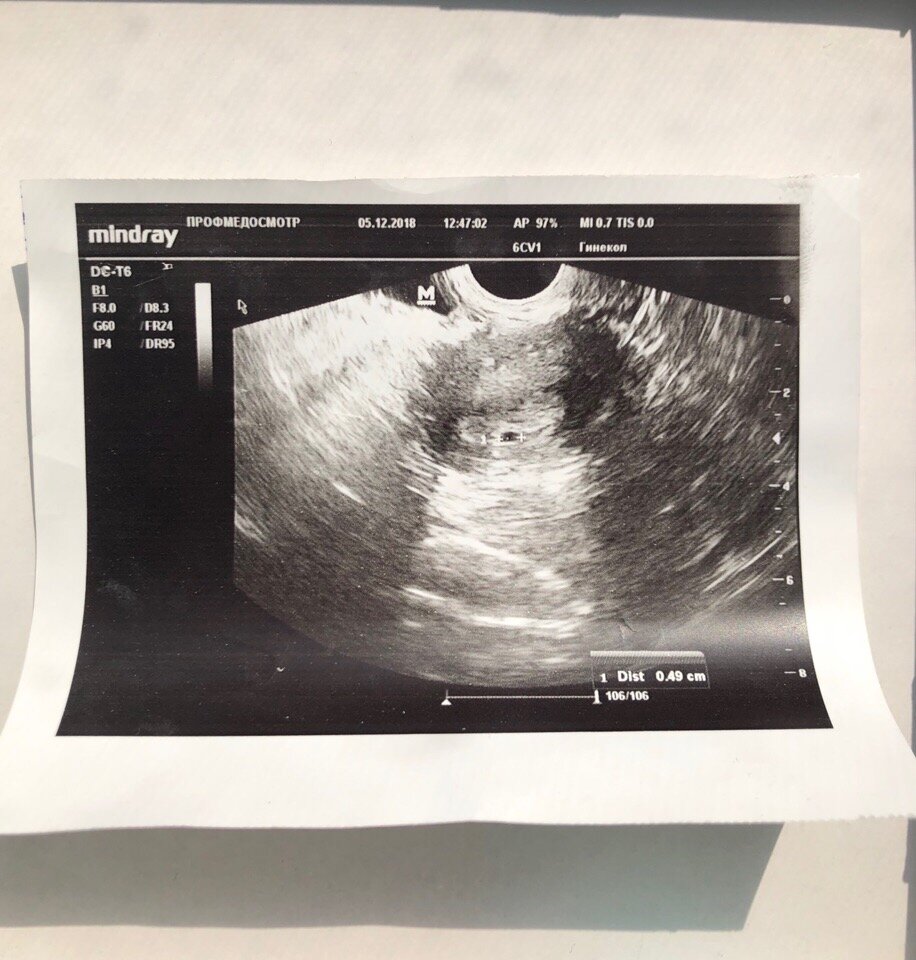

Мы были счастливы и до конца не верили, что все получилось. Она такая бледная, едва заметная. 5 декабря мы пошли на УЗИ и увидели маленькое плодное яйцо размером всего 4,5 мм. Настоящее счастье для каждой девушки узнать, что ты беременна)